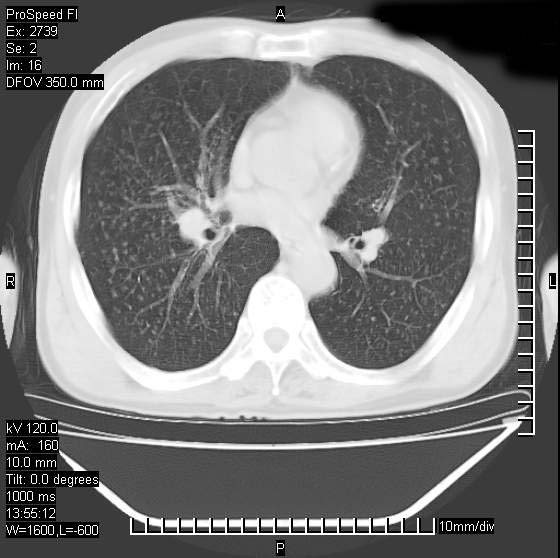

以下是引用andymaomao在2007-12-7 15:54:00的发言:[br]1.双上肺陈旧肺tb灶;[br]2.双中上肺矽肺;[br]3.双肺气肿;[br]4.图中箭头所指乃下腔静脉。

以下是引用山之魂海之韵在2007-12-7 18:59:00的发言:[br]支持矽肺,左肺上叶陈旧性结核,肺气肿。箭头所指乃下腔静脉。下腔静脉显影比主动脉显影迟,增强动脉后迟可以是不均匀的。

以下是引用chengjiaqiu1在2007-12-7 17:49:00的发言:[br]矽肺,左肺上叶陈旧性结核,肺气肿。中箭头所指乃下腔静脉。